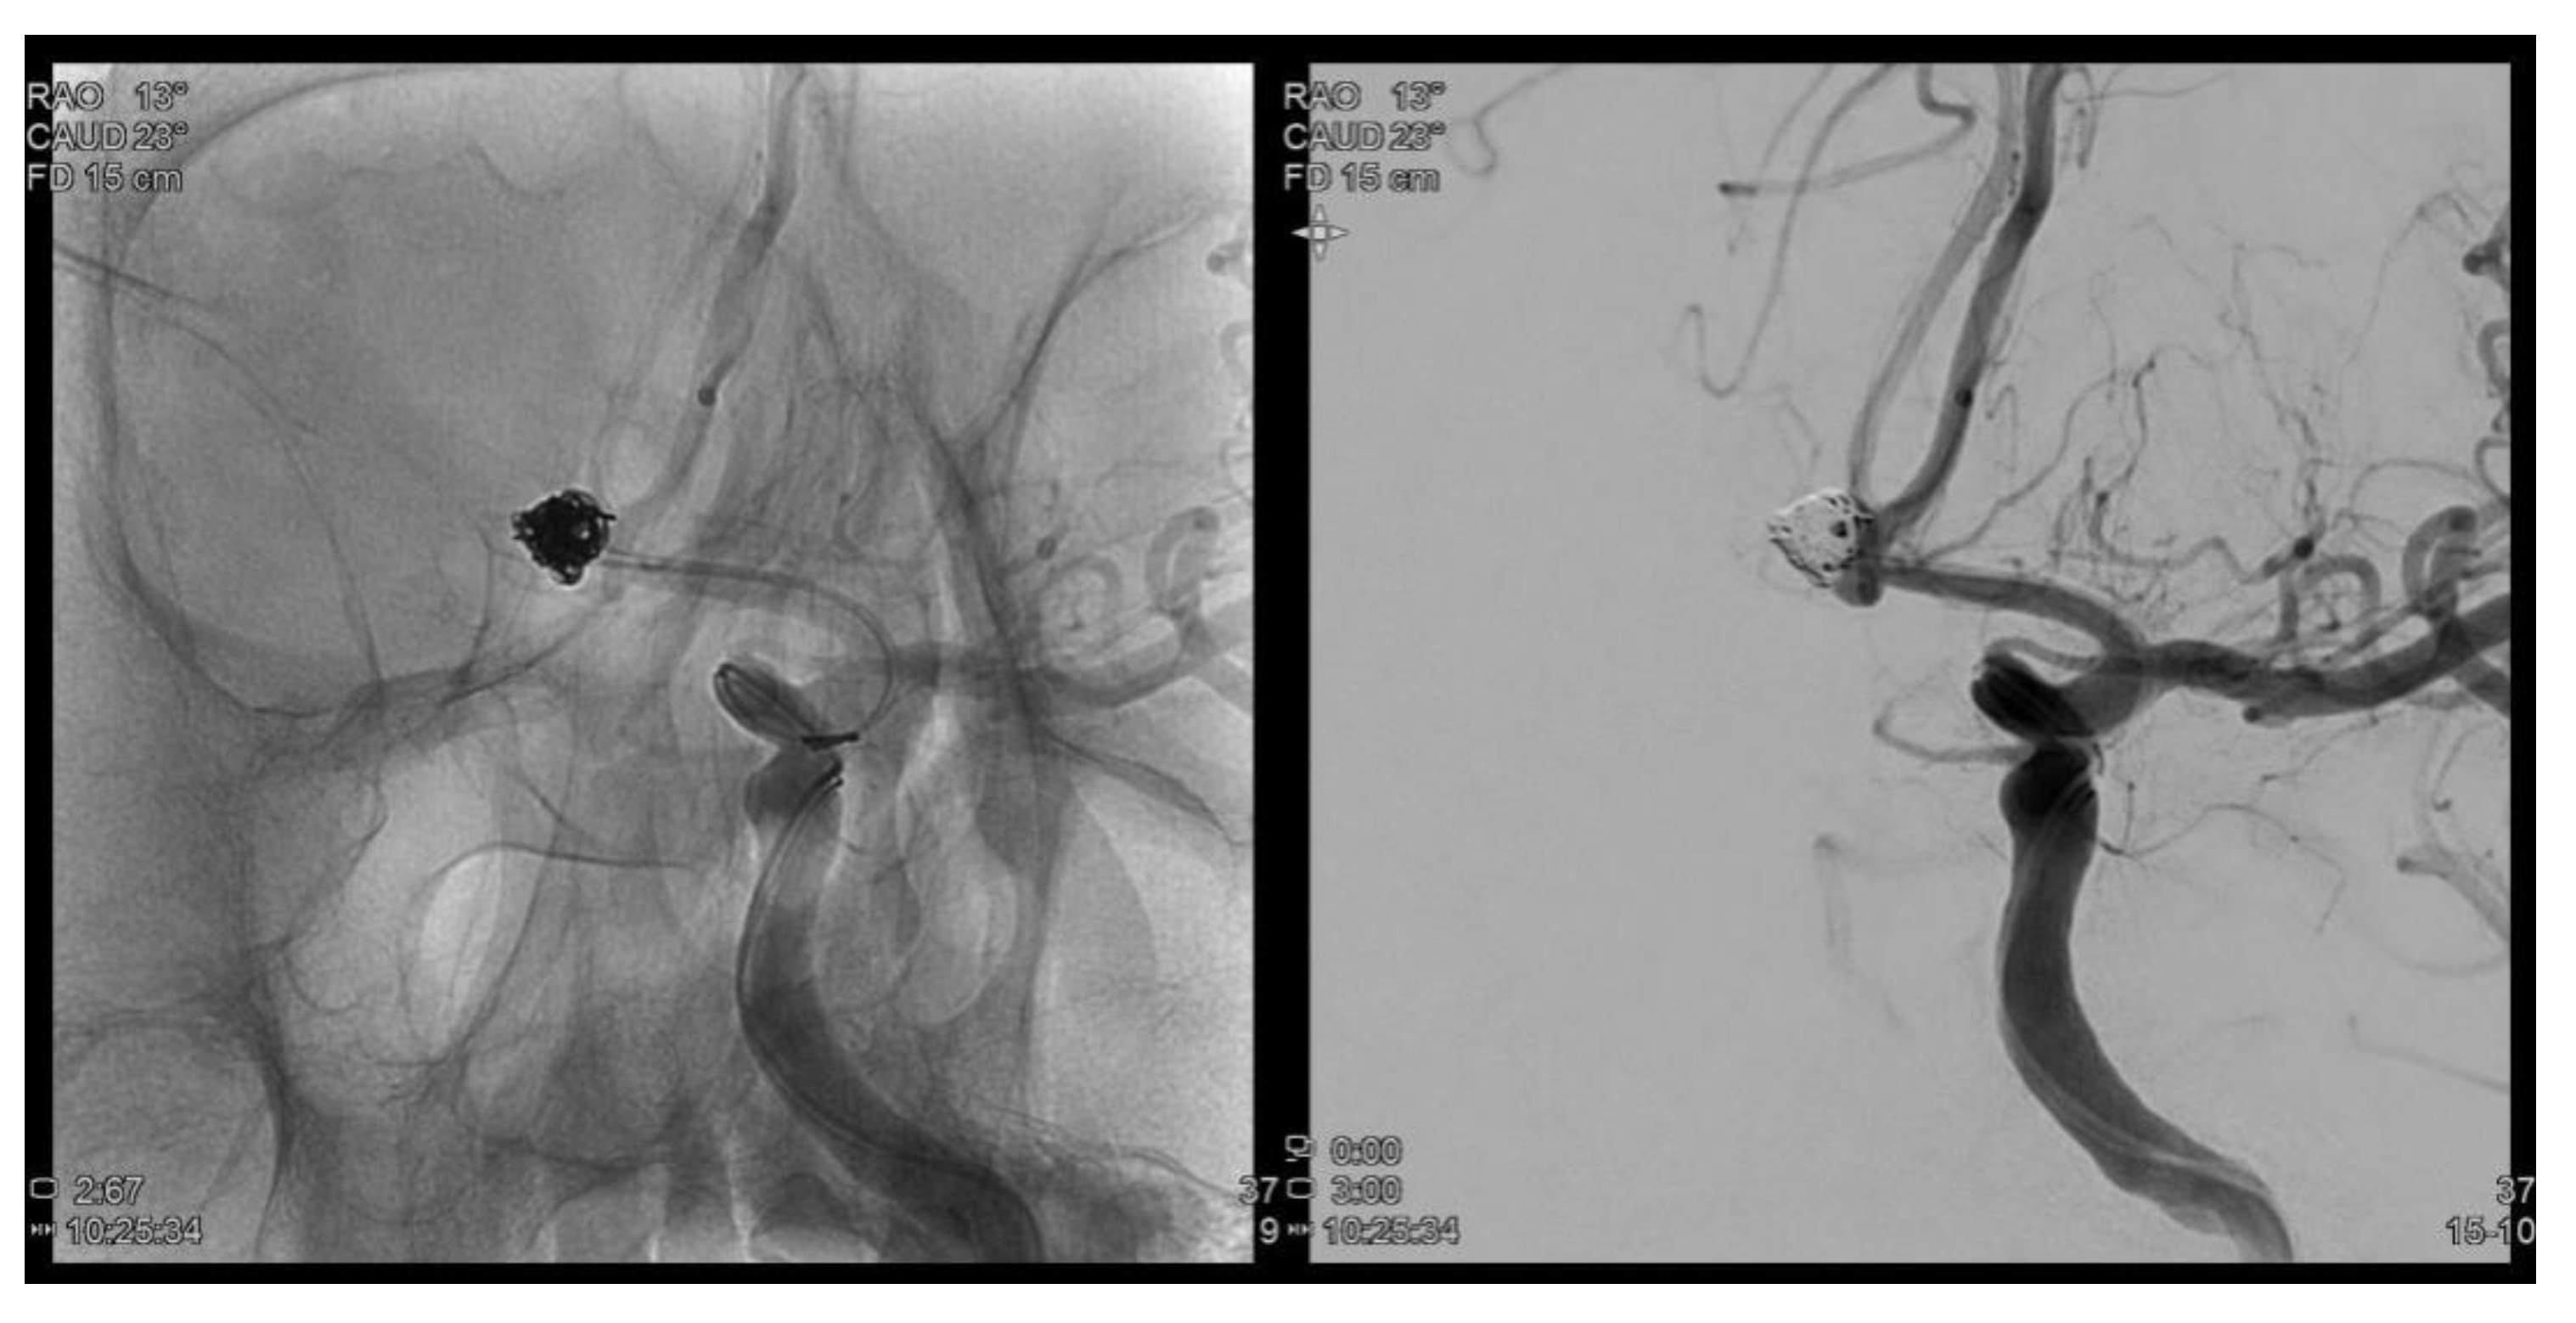

A 72-year-old man presented one month ago with a sudden pulsating continuous headache with anumeric rating scalescore of 8. Brain magnetic resonance imaging and brain magnetic resonance angiography were performed to identify structural lesions. A cerebral aneurysm of 6.2 mm in maximal diameter was detected in the anterior communicating artery (ACoA), and the patient was transferred to the neurosurgery for coil embolization. Cerebral angiography performed before the procedure found no stenosis or sign of vasospasmof the carotid and intracranial arteries. Coil embolization was successfully completed (

Figure 1). However, the day after the procedure, the patient complained that a small fixed dark gray square was visible on the inferior central area and felt that hisvision was out of focus. The confrontation test did not show prominent visual field defects. On anterior segment examination, no abnormality was observed in both eyes. Intraocular pressure (IOP) measured using non-contact tonometry was 15/16, the corrected visual acuity was 20/20 in the right eye and 20/63 in the left eye, and pupillary light reflexes were intact. The retina showed partial whitening (0.5 DD) in the perimacular area at the 12 o’clock position, indicating the possibility of cilioretinal artery occlusion (CLRAO). Moreover, there was a branch retinal artery occlusion 1 DD (disc diameter) away from the optic disc to the inferior temporal area, accompanied by inner retinal edema, and macular pigment epithelial detachment (PED) was detected.